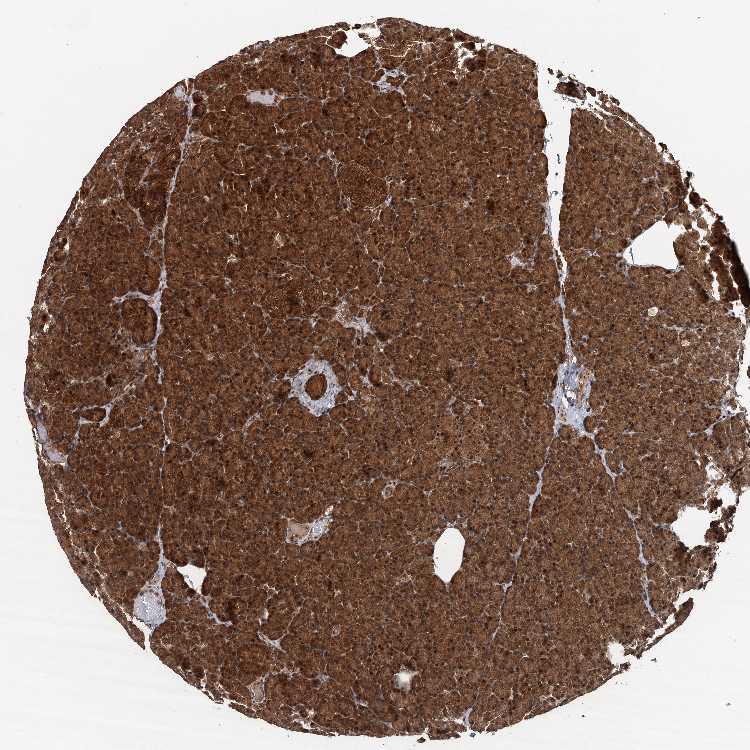

PANCREAS - Antibody stainingi

Antibody staining in the annotated cell types in the current human tissue is reported as not detected, low, medium, or high, based on conventional immunohistochemistry profiling in selected tissues. This score is based on the combination of the staining intensity and fraction of stained cells.

Each image is clickable and will lead to virtual microscopy that enables deeper exploration of all samples and also displays staining intensity scores, fraction scores and subcellular localization as well as patient and tissue information for each sample.

Antibody HPA041222Antibody HPA043531Antibody CAB037202Antibody CAB037209

Exocrine glandular cells LowLowHighHigh

Pancreatic endocrine cells Not detectedLowHighHigh